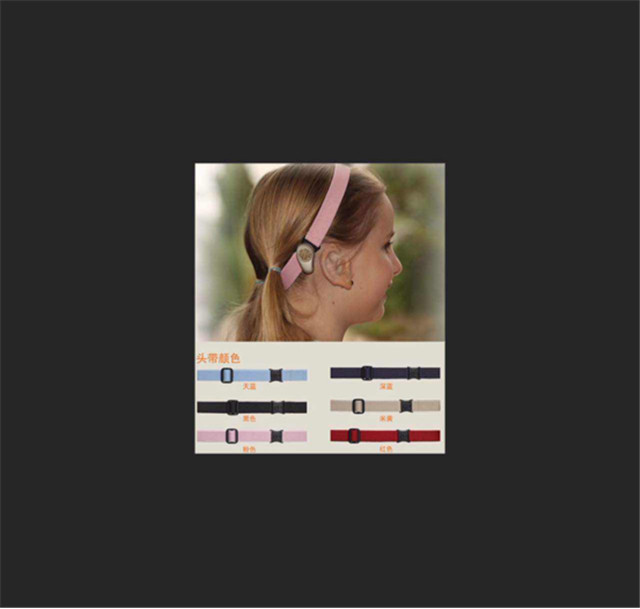

但是孩子的家長因?yàn)椴欢郧皼]見過,對(duì)于性價(jià)比產(chǎn)生了懷疑,后來在公司的幫助下給孩子調(diào)來一臺(tái)樣機(jī),孩子試戴后效果理想,孩子家長才放心。經(jīng)過幾次的接觸家長感覺我們比較可信,最后本著讓孩子聽好,佩戴舒適的原則最終選擇了PontoPro(頭帶式骨導(dǎo)助聽器)

這種助聽器佩戴起來非常舒服,把助聽器固定在頭帶上,頭帶的樣子就和平時(shí)的裝飾頭帶一樣,非常柔軟且有彈力,色彩多樣可選,比以前老式的頭箍式的要好的多。

附機(jī)器圖片: